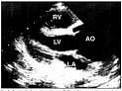

问题 男,近视,四肢细长,行超声检查心脏如图,最可能诊断为?(?)

选项 A.正常心脏图像 B.高血压心脏病 C.马方综合征 D.以上均不是 E.以上均是

答案 C